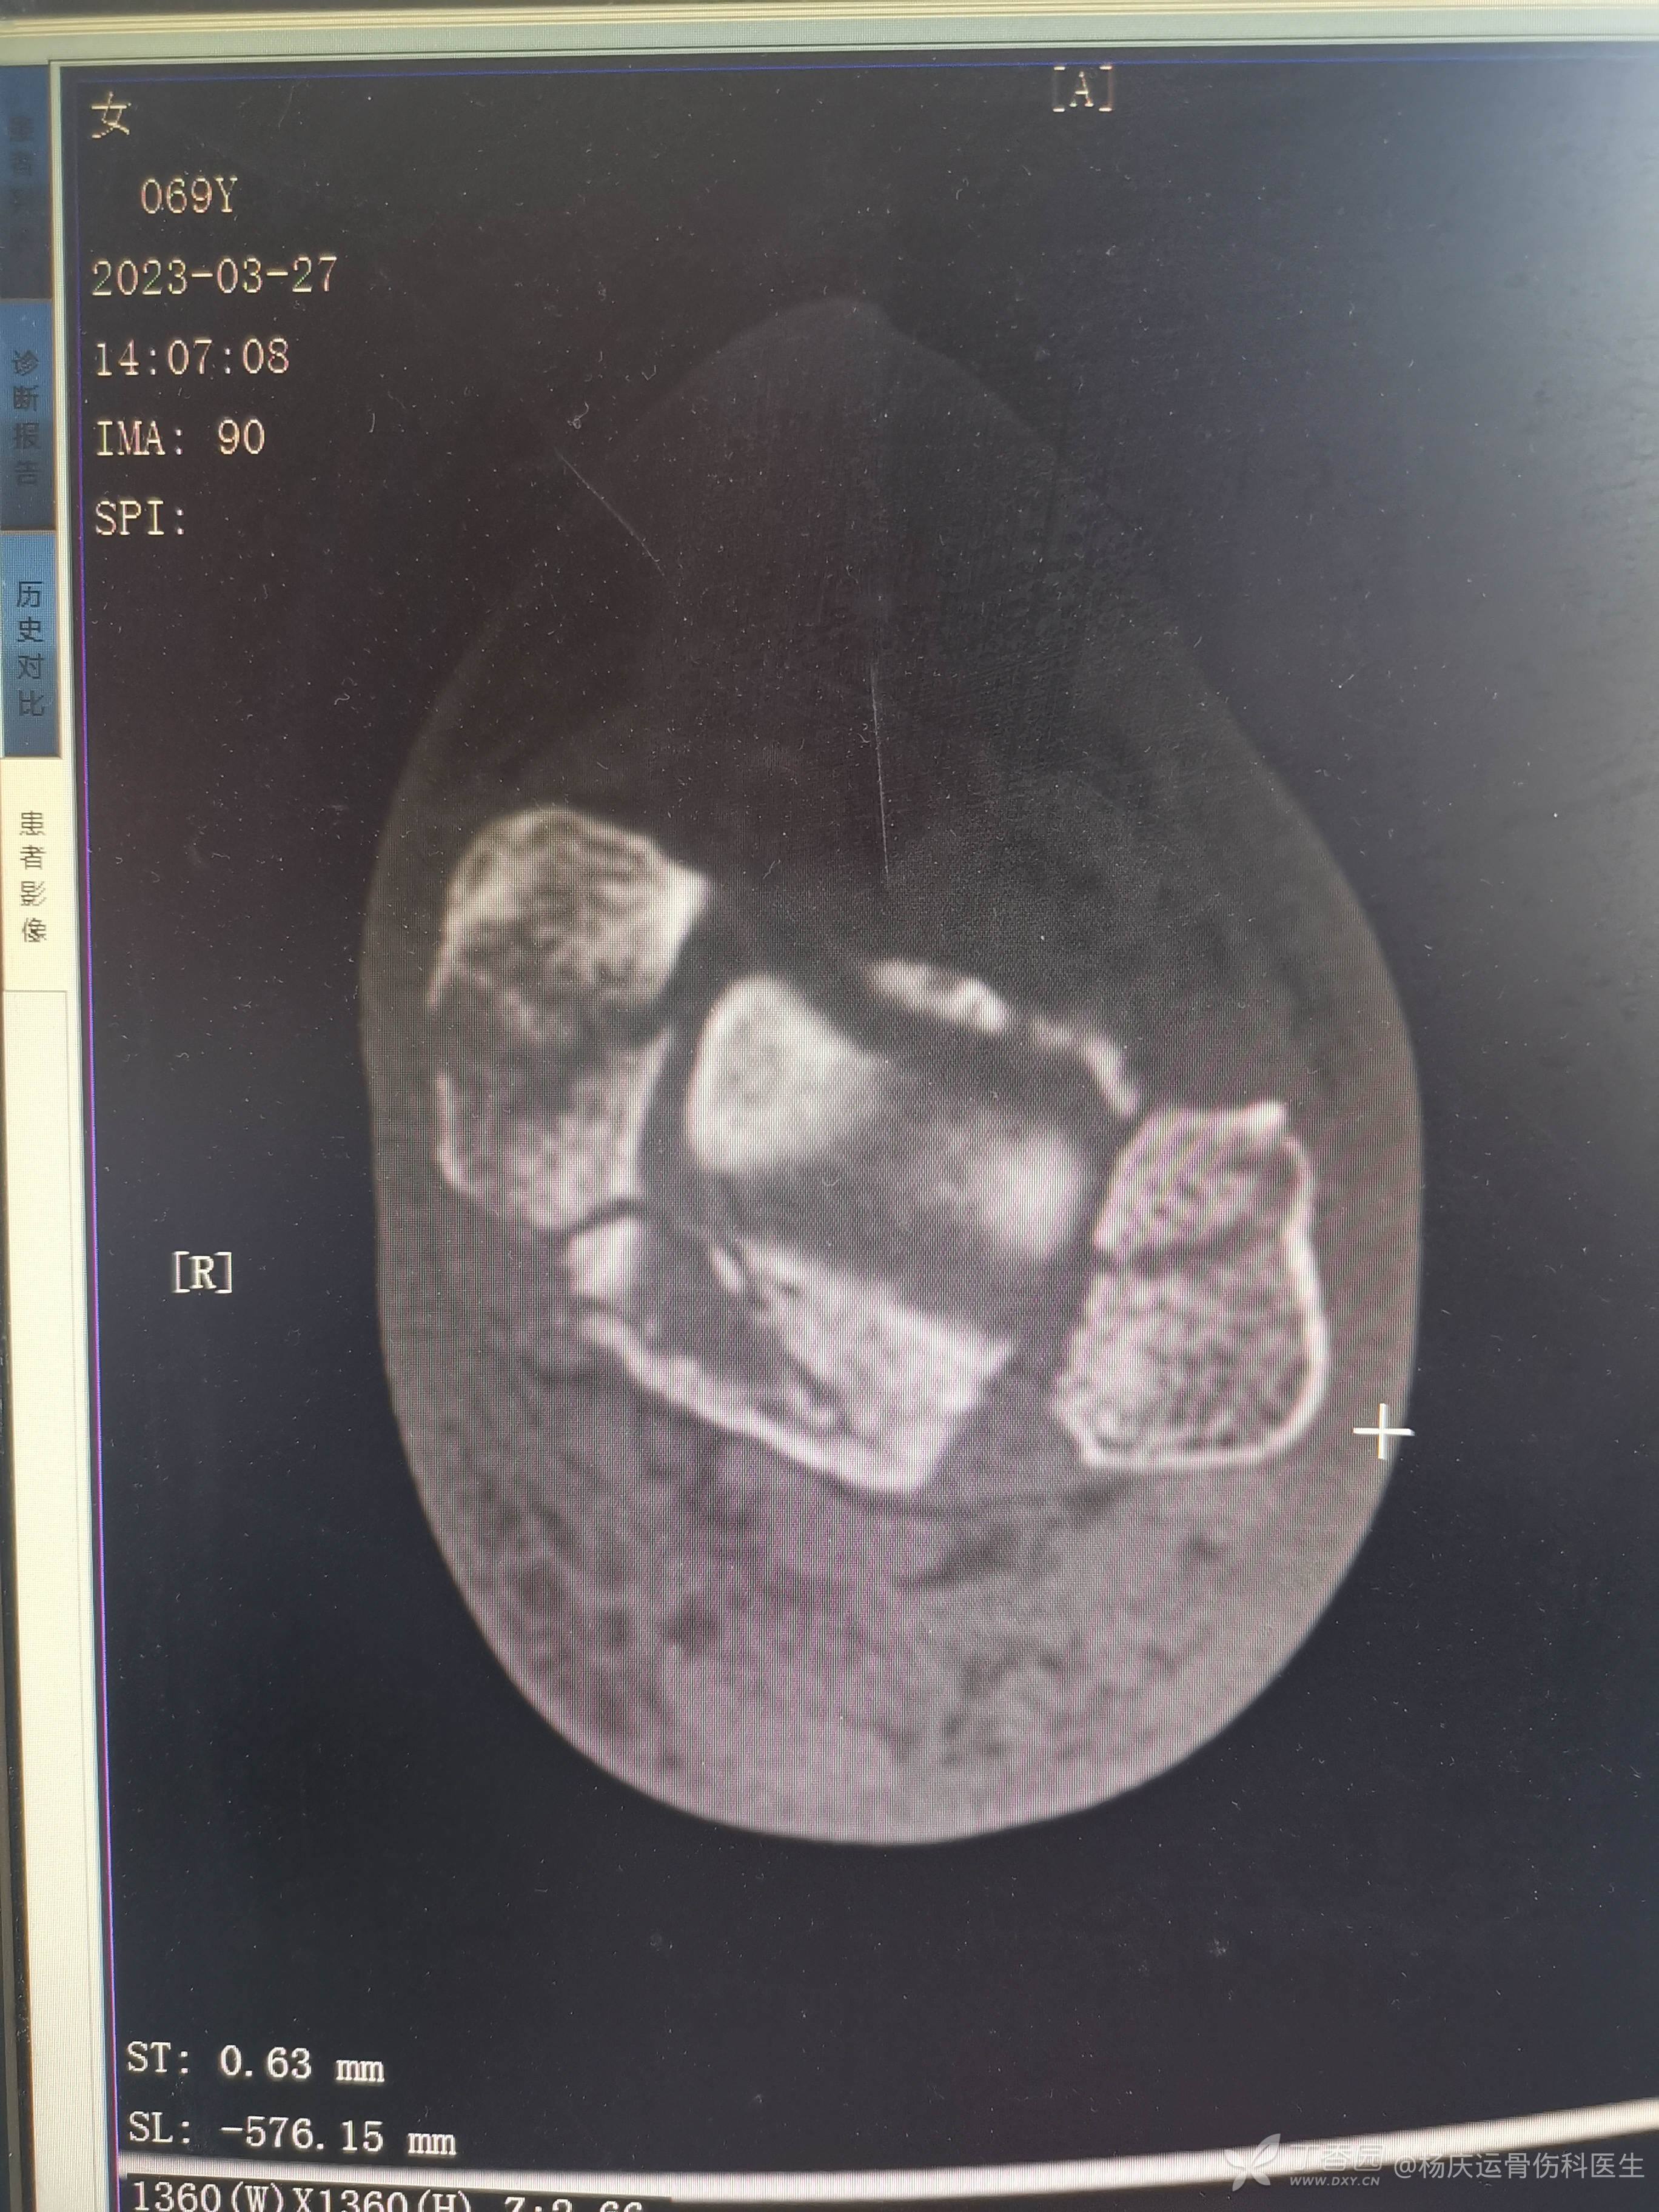

复位前CT